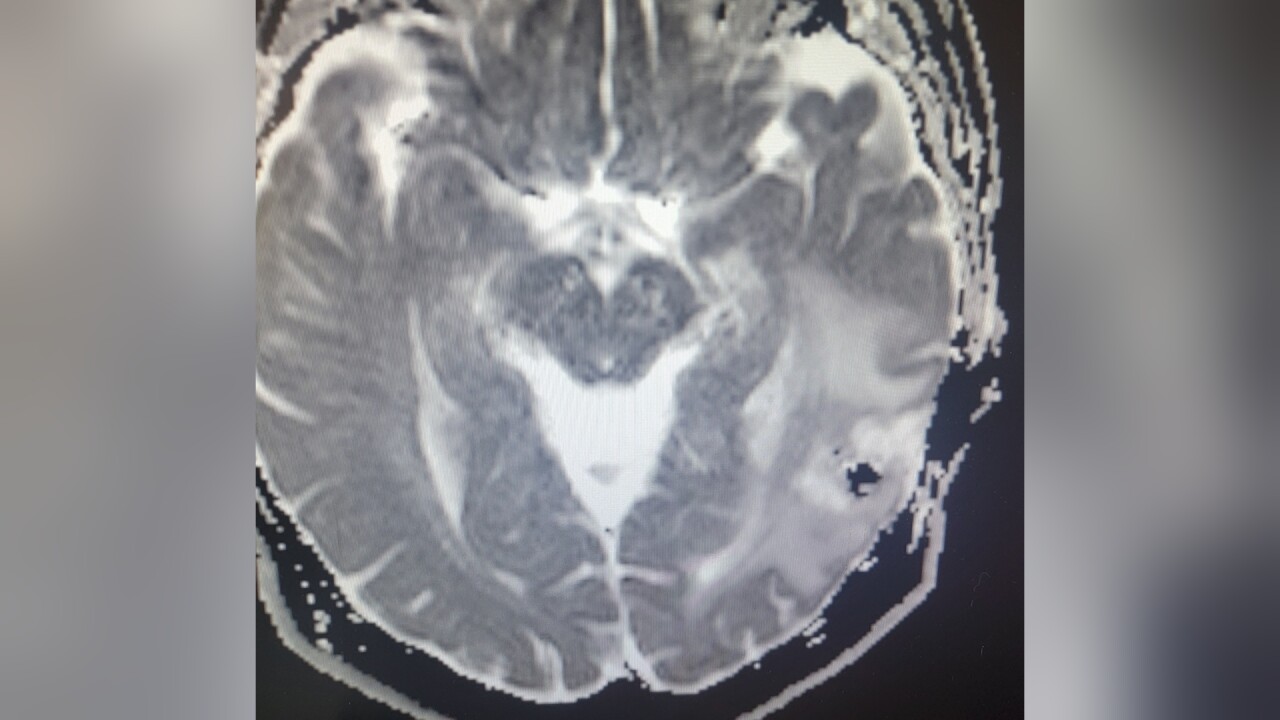

The fire truck pulled over, and Sean basically blacked out. By the time he got to the hospital and had an MRI taken, the diagnosis was clear: Sean had a large glioblastoma - a tumor -on the back left part of his brain. Two days later, he was in surgery.

When Sean did wake up, it was to good news. Billings Clinic Neurosurgeon Dr. Vance Fredrickson was able to remove almost the entire tumor.

"The goal is always to get as much as you can safely - there's a longer survival if you get more," Fredrickson said. "But there's also a shorter survival if you cause major deficits trying to get the tumor out."

Deficits meaning basic motor functions - speech, sight, etc. For the next year, Sean looked and felt great, and the Laurel community rallied behind him, holding a number of fundraisers to help with his recovery. But then the tumor started to grow back, and Fredrickson needed to go back in.

"He said, 'I want to go a little deeper if that's ok, but you’re probably going to lose some of your vision,'" Sean remembers of the conversation. "I said I’m totally fine with that - just get that out of my head."

Once again, the outcome was extremely positive: Sean's most recent scans showed the tumor shrinking, and he has nothing but praise for all of the medical personnel involved. But life is much different now.